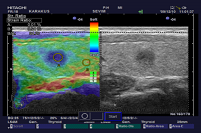

Bulgular: Fizik muayenede ağız boşluğu doğal gorunumdeydi. Boyunda palpasyonla ağrı ve hassasiyet mevcuttu. Tetkiklerde hipertiroidi saptandı. Servikal grafide yeni gelişen trakeal darlık ,tiroid ultrasonografide kanlama artmış, parankimde tiroidit saptandı.Hastaya oral Metilprednizolon Sodyum Suksinat, non-steroidal anti-inflamatuar ve betablokor tedavisi veridli. Hastanın şikayetleri tedavi altında geriledi. Tum bu bulgular ele alındığında hastada on planda radyasyon tiroiditi duşunuldu.